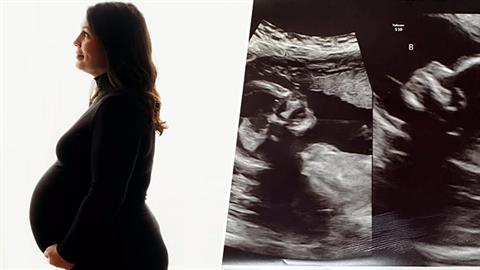

Η μαιευτική βία είναι ο όρος που χρησιμοποιείται για να περιγράψει το φαινόμενο της βίας που δέχονται οι γυναίκες κατά την εγκυμοσύνη, τον τοκετό και την λοχεία

Το όνειρό της ήταν να γίνει μανούλα και, επιτέλους, πραγματοποιείται

Οι γιατροί της είχαν ξεκαθαρίσει πως είναι αδύνατο να μείνει έγκυος φυσικά, αλλά... έμεινε!

Σήμερα είναι 5 μηνών και υγιέστατες!

Πρόκειται για ένα εξαιρετικά σπάνιο φαινόμενο!